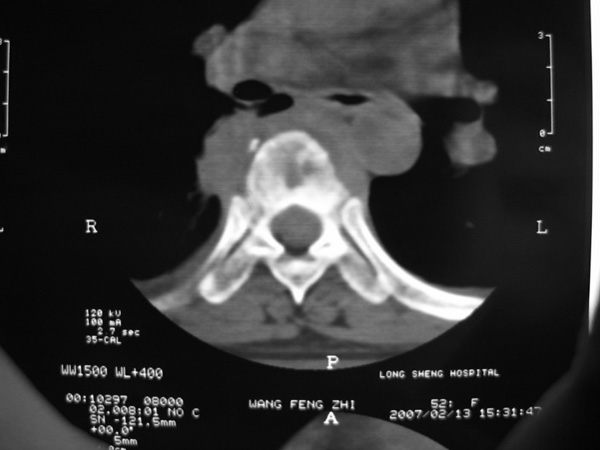

女,45岁,胸背部疼痛2个月。t6、7胸椎病变。

椎旁肿胀的软组织内可见气泡影,对脊柱的化脓性和结核性的鉴别有帮助吗?

胸椎体骨质破坏伴死骨形成,椎周环状软组织肿胀,范围较长,考虑胸椎结核伴冷脓肿形成。鉴别;1转移性肿瘤;椎弓根骨质破坏多见,软组织肿块局限。椎间隙尚存。有原发肿瘤病史。2,淋巴瘤;骨质破坏 然骨皮质轮廓线尚存,当椎管骨示环状软组织影时有一定特异性。病变较局限。建议mri增强,观察冷脓肿与软组织肿块很有帮助。

胸椎结核与脊柱椎体化脓性脊柱炎,从影像特点很难鉴别,本例具有二者的共性特点,建议结合临床鉴别以下,我考虑:1 胸椎结核.2 化脓性脊柱炎.原因: 椎体溶骨性破坏,但未见死骨.我认为大家说的气泡是假象。